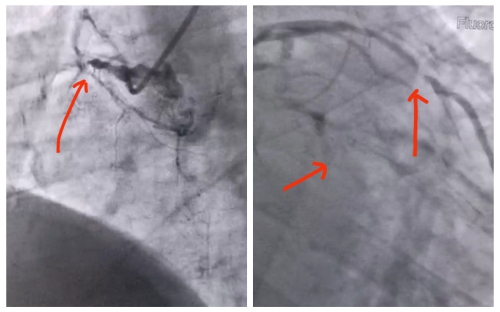

右冠完全闭塞,前降支完全闭塞,对角支狭窄90%以上

江先生被送到省医时距发病已过去6小时,呈心源性休克状态,心率130次/分、血压仅70/40mmhg,立即置入主动脉球囊反搏(IABP)装置抢救,随后冠脉造影发现心脏上所有的三支主要血管全闭塞了!其中右冠状动脉、左回旋支慢性闭塞,左前降支近端急性闭塞,仅一高位对角支(分支)有血流且狭窄90%,此类病变死亡率极高,可谓命悬一线。